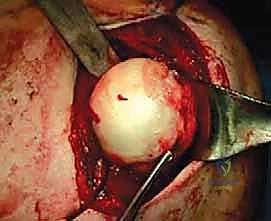

الخطوة الثالثة: الوصول الجراحي للآفة

يتم عمل شق جراحي دقيق (عادة من الجهة الأمامية أو العلوية الممتدة) للوصول إلى رأس عظم العضد. يتم إبعاد العضلات والأوتار المحيطة بلطف شديد (بتقنيات الجراحة المجهرية التي يبرع فيها الدكتور هطيف) للحفاظ على التروية الدموية للأنسجة.

يتم تنظيف موقع آفة هيل ساكس من الأنسجة الليفية للوصول إلى عظم حي ينزف، مما يحفز عملية الالتئام. بعد ذلك، يتم إدخال الطعم العظمي المُشكل في مكانه.

يستخدم الدكتور هطيف براغي طبية خاصة (غالباً براغي التيتانيوم المجوفة أو البراغي القابلة للامتصاص) لتثبيت الطعم بقوة فائقة في رأس عظم العضد. يتم غرس رؤوس البراغي تحت مستوى سطح الغضروف لضمان عدم احتكاكها بالجوف الحقاني أثناء حركة الكتف.